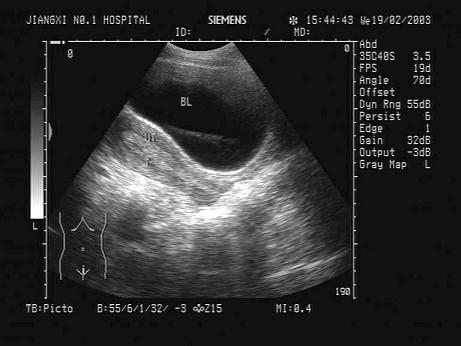

问题 女,16岁,有性生活史,因停经35天。根据B超检查声像图如下,合理的超声诊断意见为?(?)

选项 A.动态观察 B.早孕 C.宫外孕可能,建议经阴道超声检查 D.抗感染治疗 E.内膜过度增生

答案 A